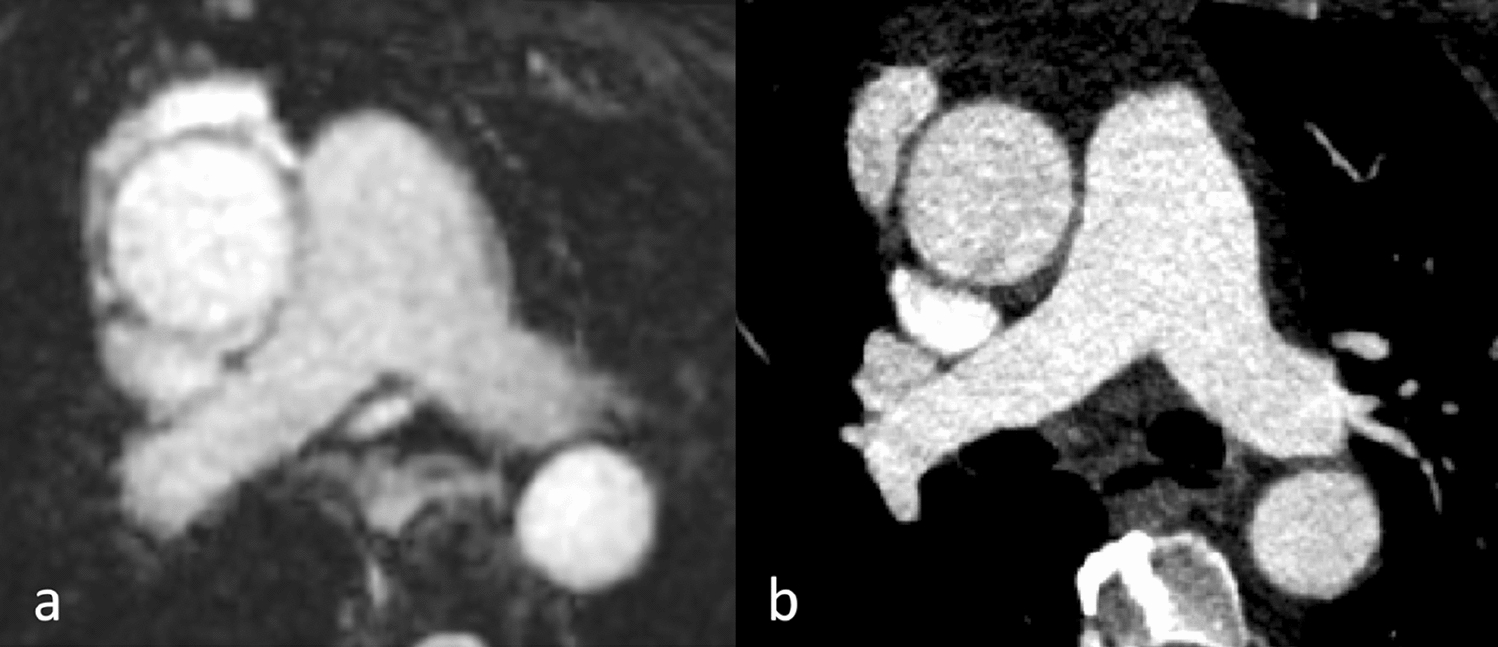

Fig. 6

A patient presented after a near-collapse episode at rest. Hypotension and a blood pressure difference between arms were observed in the Emergency Department. The CT scan ruled out aortic dissection. Axial reformation of an enlarged view of the pulmonary arteries in MRA (a) and CTA (b). Excellent image quality in both modalities despite a lower resolution in the MRA (a)